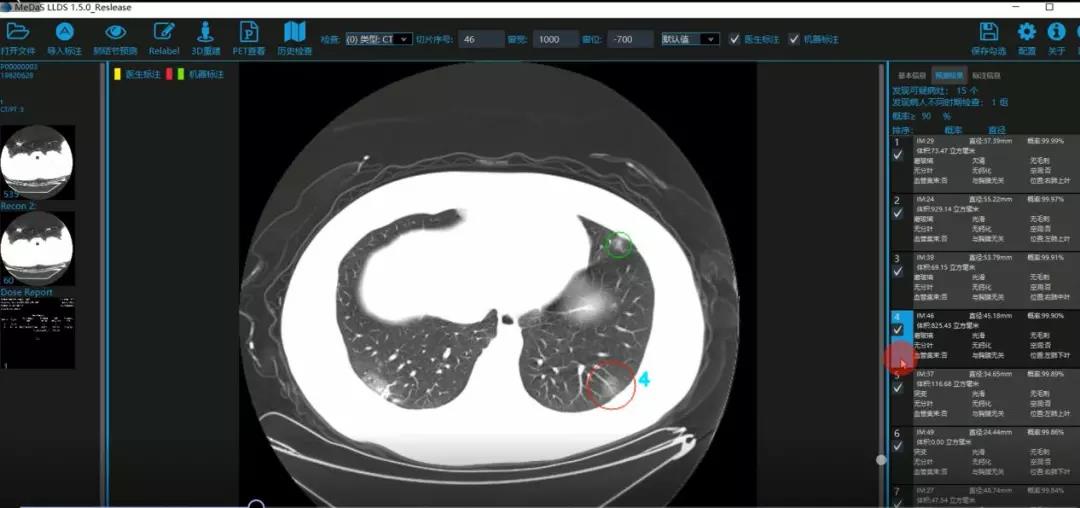

西电tyc33455cc智能软件与系统新技术研究所副教授张亮的爱人是西安交通大学第二附属医院抗疫一线的影像科医生,疫情发生以来,他们讨论最多的就是新型冠状病毒感染者的早期诊断问题。作为一名医护家属,身为高校科研工作者,张亮深知快速准确地诊断新冠肺炎早期患者对控制和防治疫情的重要性和挑战性。他与团队成员主动出击,通过远程网络会议,在前期医学影像处理的研究基础上加速科研攻关,反复讨论方案,屡次设计模型,与上海宽带技术及应用工程研究中心、上海交通大学医公司附属瑞金医院等合作单位的人员多次标注整理患者肺部CT影像数据到深夜。与此同时,他们依托上海瑞金医院、西安交通大学第二附属医院等的新冠肺炎疑似、确诊患者肺部CT影像,通过综合分析新冠肺炎患者的肺部CT影像特点(磨玻璃、体积大小、位置等特征),张亮团队加快技术攻关,设计开发了基于深度学习的新型冠状病毒的早期检测筛查模型系统。

对应新冠肺炎CT病灶检测效果

令人欣喜的是,通过对实际门诊数据排查测试,该模型可以减轻医护人员近80%的工作量,新冠肺炎患者的检测召回率超过95%。目前,模型系统正在进行最后的调试工作,很快投入到“战疫”一线,缓解医护人员紧缺、确诊检测工作耗时较长等问题,减少医护人员的工作时间和劳动强度,提高工作效率。